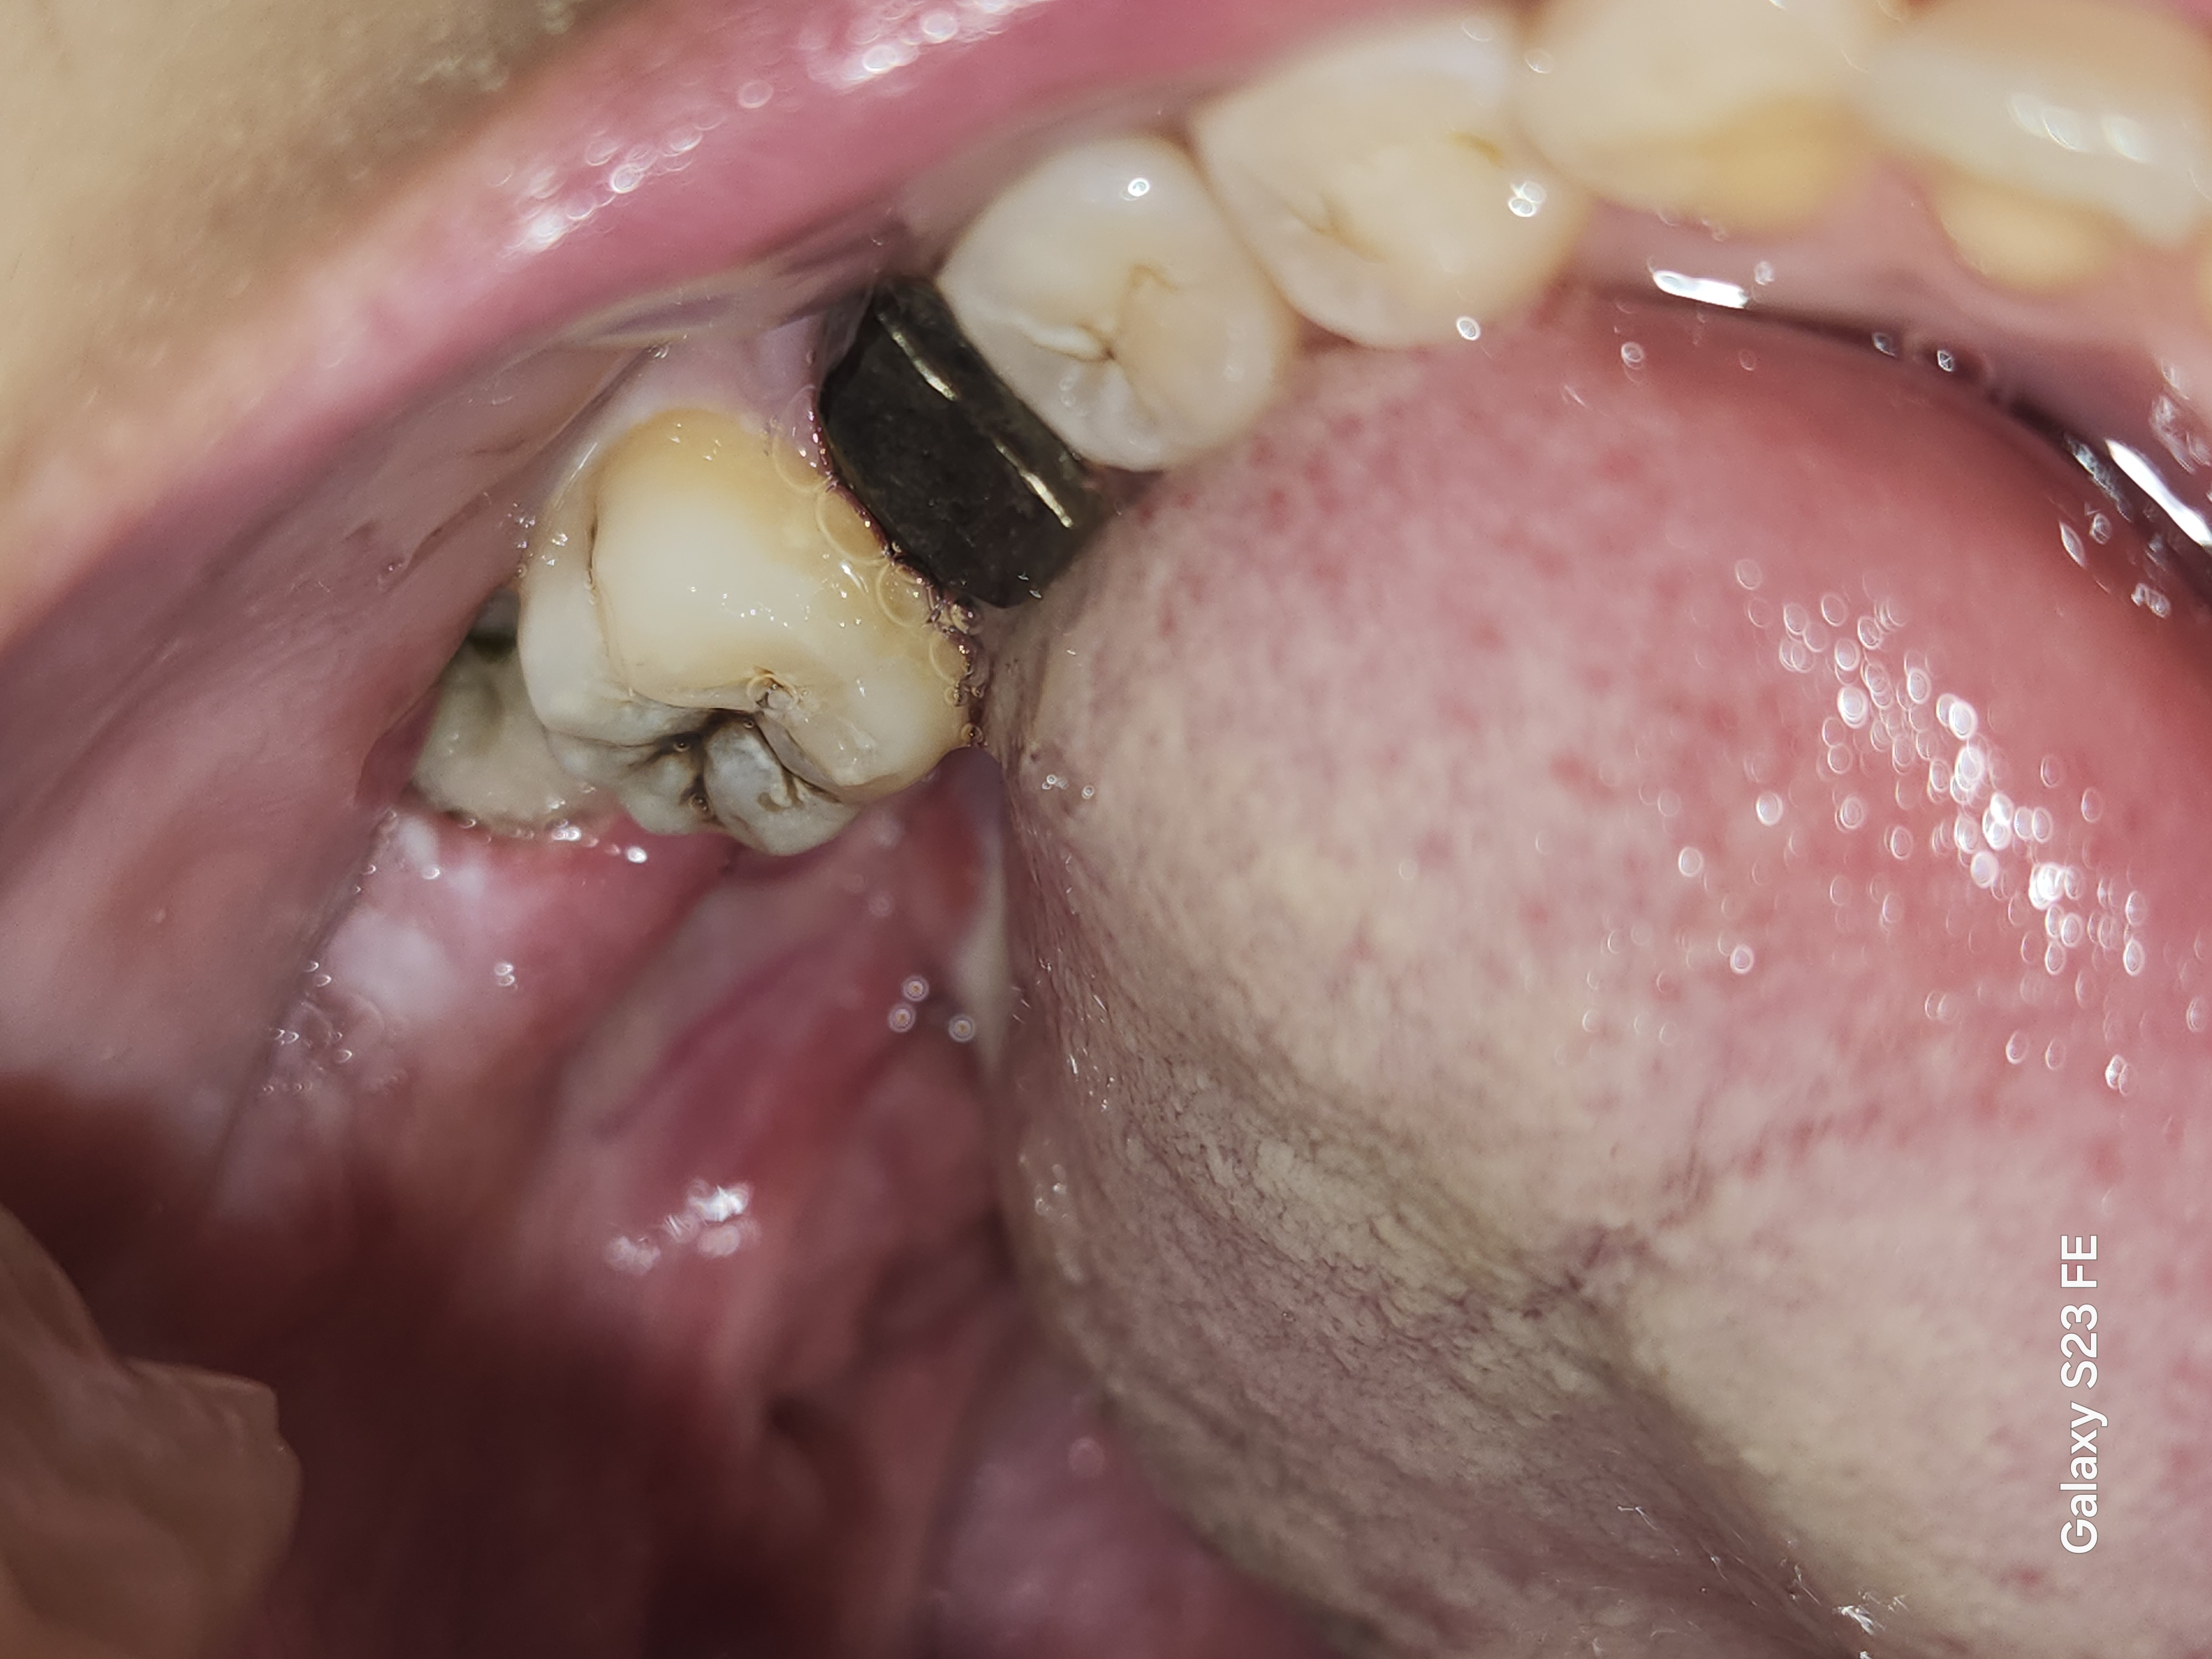

親知らず抜歯後、抜糸もしましたが歯茎の中に黒い糸のようなものがあります。